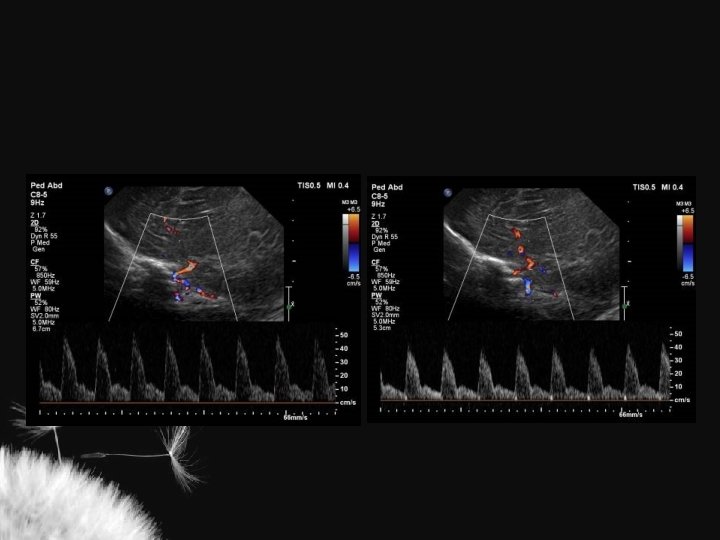

Artérias cerebrais normais

Valores normais ACI ACA AB Vs (cm/s) 50 + 15 42 + 15 41 + 16 Vd (cm/s) 11 + 4 11 + 5 11 + 4 TAMX (cm/s) 22 + 6 21 + 9 19 + 7 0, 77 + 0, 08 0, 73 + 0, 08 0, 72 + 0, 09 RI Deeg KH. Neuroradiology 32: 60 -63

Índice de resistência (IR) nas artérias intracranianas ACA ACI Martin (1982) 0, 75 + 0, 03 Jorch (1986) 0, 74 + 0, 06 Lipman et al. (1982) 0, 79 + 0, 04 Perlman et al. (1985) 0, 66 + 0, 06 Deeg (1989) 0, 73 + 0, 08 AB 0, 77 + 0, 07 0, 73 + 0, 06 0, 77 + 0, 08 0, 72 + 0, 09 ACA artéria cerebral anterior, ACI artéria carótida interna, AB artéria basilar IR pré-termo 0, 79 + 0, 02 IR > 2 anos 0, 50 + 0, 08

Considerações IR = S – D S Perfusão Q = A x TAV Aumento da PIC 1. Aumento da velocidade sistólica 2. Diminuição da velocidade diastólica Compressão fontanelar 1. Normal – aumenta até 6% 2. Diminuição da complacência craniana – > = 20%

Condições extracranianas que alteram o IR Fator Aumento do p. CO 2 Aumento da FC PCA Pneumotórax Isquemia miocárdica Policitemia Anemia Indometacina Surfactante IR